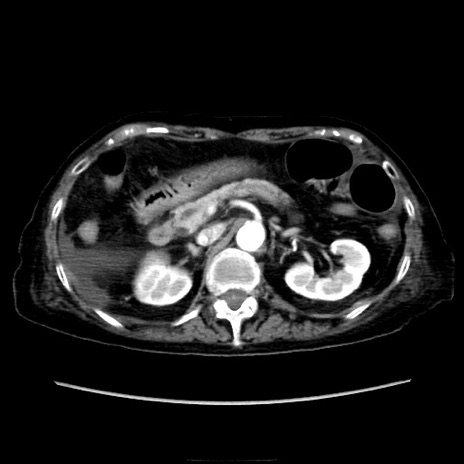

症例40(横断像)

横断像